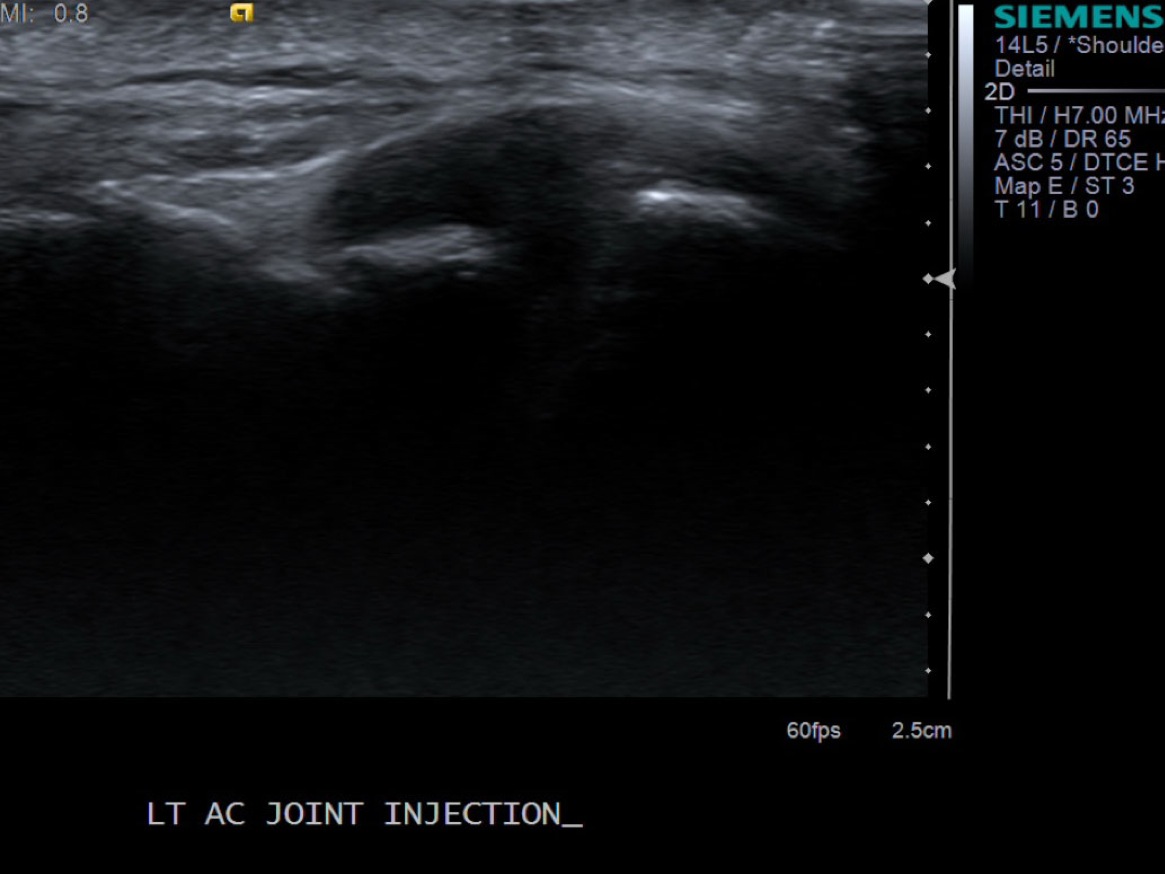

3. Place probe parallel to the joint and mark probe location and probable injection site

• descriptiondescription